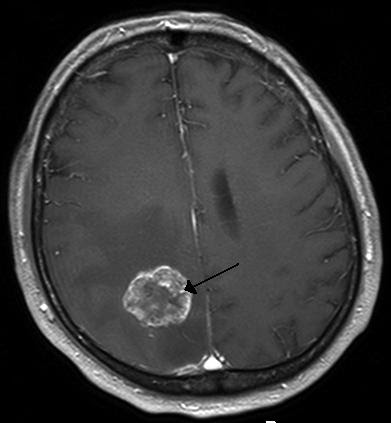

척수, 뇌간에 발생하지 않았다면 다른 치료 없이 완치가 가능한 양성종양도 있습니다. 반대로 주위 조직으로 퍼져나가고 성장 속도 빠른 악성종양도 있습니다. 뇌종양의 치료를 어렵게 만드는 점은 양성이든 악성이든 경계가 불분명하다는 점이죠. 특히 뇌종양을 진단받고 심각한 경우는 치료 시기를 놓쳐 주변의 정상적인 뇌 조직이 이미 망가졌을때 입니다.

눈으로 체크하기란 어렵습니다. 초기 증상을 잘 파악하는 것이 무엇보다 중요하죠. 스스로 뇌압을 조절하는 능력이 있는 우리의 뇌는 종양이 크게 변하기 전까지는 증상을 보이지 않기 때문에 스스로 뇌종양의 초기 증상에 대해서 아는 것이 좋습니다.

이러한 뇌종양은 뇌 조직이나 뇌를 싸고 있는 막에 발생한 종양을 뇌종양이라고 부릅니다. 그리고 머리뼈나 주위 멀리 떨어진 부위에서 뇌 조직이 뇌막으로 옮겨진 종양도 뇌종양이라고 봅니다.